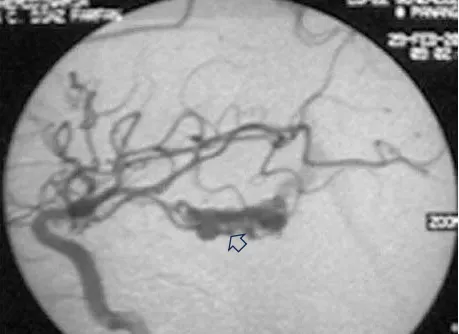

首次手术仅仅三个月后,令大卫一家担忧的事情还是来临了。大卫在学校突然昏迷,紧急送往医院后,检查为左侧颞角的AVM导致脑室内出血(图ab)。Spetzler-Martin分级4级:S1V1E1/A1B0C0,供血来自AChA(脉络膜前动脉)。

图(a)左侧ICA造影,侧位和lPChA